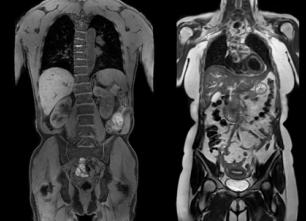

За последнее десятилетие, МРТ доказало свою эффективность и информативность при диагностике гинекологических заболеваний. Информативность данного диагностического метода обусловлена отличной визуализацией половых органов, благодаря высокому контрасту мягких тканей. К тому же этот метод полностью неинвазивный, что особенно ценно для женщин детородного возраста.